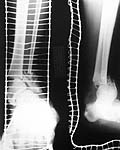

Middle aged adult was injured while travelling in a train(accidentally put his leg out). Presented with injury to left lower leg. Lacerated wound over the fibular fracture. Also another wound over the foot anterolaterally. No deficits.

On day one wound debridement followed by calcaneal traction done. Needs further stabilisation and a small split graft laterally. At present the fragments are putting pressure on the anterior skin. Will be happy to get your opinion on possible methods of stabilisation.

Day 1

Traction